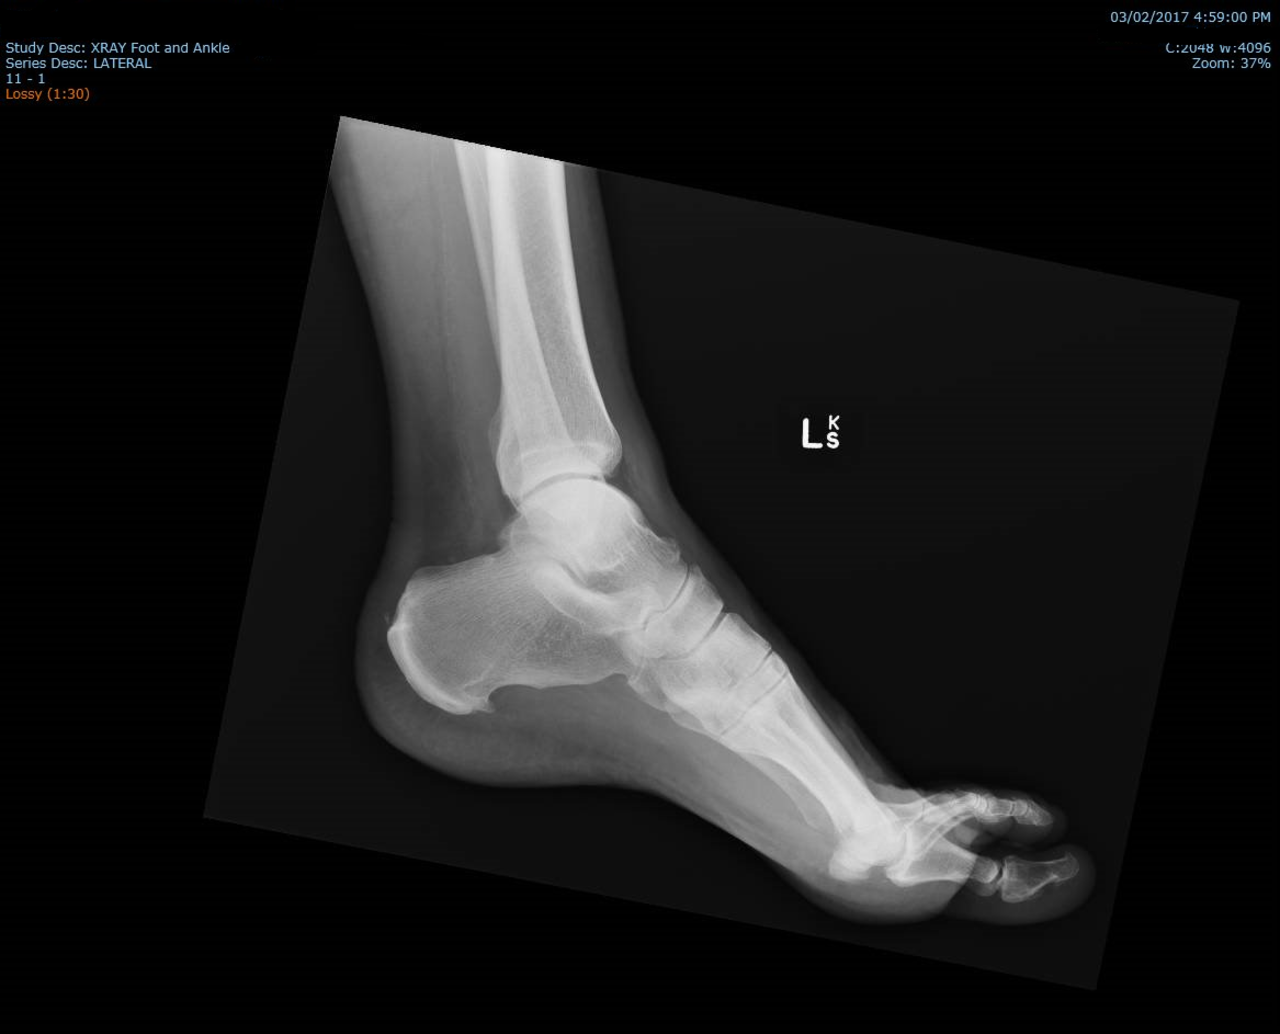

Ostroga piętowa. Wreszcie wiesz, jakie są przyczyny i objawy, na czym polega leczenie i jakie ćwiczenia pomagają Ostroga piętowa to problem nawet 15% ludzi. To schorzenie, którego leczenie jest długotrwałe i skomplikowane. Dowiedz się więcej o objawach, diagnozie i leczeniu ostrogi piętowej. 16-01-2023 12:23 MK Ostroga piętowa. Wreszcie wiesz, jakie są przyczyny i objawy, na czym polega leczenie i jakie ćwiczenia pomagają Ostroga piętowa zostaje po raz pierwszy opisana w 1900 roku. Niemiecki lekarz P. Platter widzi specyficzną bruzdę na zdjęciu RTG stopy. Ostroga piętowa. Gdzie pojawia się i jak wygląda? To narośl kostna, którą widzisz na zdjęciach RTG w okolicy wyrostka przyśrodkowego guza piętowego. Często jej pojawieniu się towarzyszy ból. Dlatego ostroga znacząco wpływa na obniżenie jakości życia. Uprzykrza codzienne czynności. Pojawiają się problemy z poruszaniem się i dłuższym staniem, które ostatecznie prowadzą do bardzo trudnych do wyleczenia wad stóp, a nawet całych nóg. Ostroga piętowa. Poważny problem społeczny. Ból w okolicy pięty dotyka coraz więcej osób. Badacze Australijscy mówią o 15% całej populacji, a Amerykańscy szacują, że 7% osób po 65 roku życia cierpi na to schorzenie. Jak wygląda ostroga piętowa na zdjeciu RTG - foto by IanWhyte dla Wikipedia Ostroga piętowa. Dlaczego powstaje? Może zabrzmi to dziwnie i mało profesjonalnie, ale... Do końca nie wiadomo co dokładnie powoduje pojawienie się ostrogi piętowej. Za jedną z przyczyn uważa się przewlekły stan zapalny w okolicy kości piętowej, który powstaje jako efekt długotrwałego drażnienia tkanek przez ucisk. Gdy taki stan zapalny trwa długo, to tworzy się dziobiasta narośl kostna — ostroga. Problem dotyczy osób młodych i starszych. Dotyczy tęższych i szczupłych. Dotyczy sportowców i osób bardzo lubiących swoje fotele. Może dotknąć 1 piętę, a może też 2 na raz. Wiemy, że do pojawienia się ostrogi piętowej przyczyniają się w mniejszym lub większym stopniu: praca stojąca nadwaga wiek płeć intensywność uprawiania sportu płaskostopie źle dobrane buty Co ciekawsze, u 61% osób ostroga piętowa pojawia się zupełnie bezobjawowo. To przypadki nieme klinicznie. Dlatego usunięcie ostrogi jest trudne i długotrwałe. Choć jest kilka dość skutecznych sposobów na pozbycie się jej. Ostroga piętowa. Jakie są objawy? Główne objawy ostrogi piętowej to: ból w okolicy pięty, zaczerwienienie i obrzęk pięty, narośl, sztywność stopy rano, po wstaniu z łóżka. Ze względu na to, że ponad 60% przypadków ostrogi piętowej jest bezobjawowa, głównym problemem nie jest sama narośl, tylko ból, jaki się z nią pojawia. Ostroga piętowa. Jaki ból wywołuje? Ten ból opisywany jest jako palący, kłujący, tępy, pulsujący lub ostry. Czasem określany jest jako „ból pierwszego kroku”, bo doskwiera najmocniej przy pierwszych krokach wykonywanych po przebudzeniu się. Przyczyna jest bardzo prosta — w ciągu nocy organizm regeneruje tkanki, a pierwsze kroki zrywają te zrosty. Ból przy ostrodze piętowej ma 3 fazy Faza pierwsza to ból, który pojawia się przy przeciążeniu stopy np. długim staniem lub biegiem. Faza druga to ból przy każdym obciążeniu — chodzeniu, bieganiu, staniu etc. Faza trzecia to ból spoczynkowy, który odczuwa się cały czas, bez względu na aktywność. Niestety, chorzy zgłaszają się na leczenie dopiero w fazie 3, kiedy po najłatwiejszym do opanowania bólu — zapalnym, nie ma już śladu, a został tylko uciążliwy ból przewlekły. Ostroga piętowa. Jak ją zdiagnozować? Ostroga piętowa. Czy jest groźna dla zdrowia i jakie są jej konsekwencje? Ostroga piętowa to bolesne i uciążliwe schorzenie, które doprowadza do braku samodzielności przy codziennych zajęciach. Nie warto zwlekać z udaniem się do specjalisty, gdy tylko pojawią się pierwsze bóle w okolicy pięty. Im wcześniej następuje rozpoznanie, tym szybciej rozpoczyna się leczenie i tym większa szansa na powrót do pełnej sprawności. Przeciąganie wizyty doprowadza do tego, że ból staje się przewlekły, a organizm, aby go nie czuć, zaczyna korygować chód. To prowadzi do urazów stóp i całych nóg. Wtedy wymagana jest operacja. Diagnoza ostrogi piętowej Aby postawić diagnozę, lekarz bada pacjenta i pyta o objawy. Zleca badanie RTG lub USG, uzyskuje bardziej szczegółowy obraz pięty. Lekarz wykonuje testy palpacyjne, i określa, czy istnieją jakieś guzki lub stwardnienia w pięcie. Zleca też inne badania, aby wykluczyć inne możliwe przyczyny bólu pięty. Fala uderzeniowa w leczeniu ostrogi piętowej Ostroga piętowa. Jakie ją leczyć? Czy ostroga piętowa sama przejdzie? Nie ma na to szans. Olewanie bólu pogarsza tylko sytuację. To wręcz świadomy wybór tego, że z bólu, który czujesz tylko przy przeciążeniu stopy, przejdzie on w ból przewlekły, który odczuwasz cały czas. Etapy leczenia ostrogi piętowej Podstawą leczenia ostrogi piętowej jest usunięcie tego, co sprzyja pojawianiu się bólu. Czyli wytężony ruch, godziny stania etc. Choć może to być trudne, chociażby ze względu na specyfikę pracy. Kolejnym etapem jest zlikwidowanie stanu zapalnego. Stosuje się do tego ostrzykiwanie (tzw. blokady), wkładki ortopedyczne, leki przeciwzapalne oraz fizykoterapię. Jeszcze do niedawna najpopularniejsze w walce ze stanem zapalnym były ultradźwięki i laseroterapia. Czy istnieją skuteczne sposoby zapobiegania ostrodze piętowej? Obecnie stosuje się już tylko falę uderzeniową. Działa ona dwojako. Z jednej strony zwiększa przepływ krwi, co zmniejsza stan zapalny. A z drugiej niszczy błonę komórkową, co blokuje przekazywanie bodźców bólowych. Sama fala uderzeniowa wywodzi się z medycyny sportowej. Swój debiut miała w niemieckiej kadrze na Igrzyskach Olimpijskich w Atlancie, gdzie wyniki jej działania były oszałamiające. Już 2 lata później, na Mistrzostwach Świata we Francji kilka drużyn stosowało zabiegi falą do przywracania zawodników do sprawności. Obecnie jest ona stosowana w rehabilitacji schorzeń, które skutecznie opierają się tradycyjnym formom leczenia. Jednym z nich jest ostroga piętowa. Fala uderzeniowa w usuwaniu objawów ostrogi piętowej Ostroga piętowa. Jaka jest skuteczność fali uderzeniowej? Falę uderzeniową stosujemy przy leczeniu ostrogi piętowej ze względu na jej nie inwazyjność i bezpieczeństwo. Najczęściej w terapii falą uderzeniową zalecamy wykonanie serii 10 zabiegów, które trwają kilka minut. Pomiędzy wizytami jest kilka dni odstępu, kiedy organizm regeneruje miejsce schorzenia. Fala uderzeniowa przynosi ulgę w bólu, poprawia sprawność fizyczną i nawet całkowicie eliminuje potrzebę przyjmowania leków przeciwbólowych. Jest metodą dużo mniej absorbującą niż tradycyjne terapie. Zabieg trwa krótko, a codzienne wizyty nie są potrzebne. Ostroga piętowa. Czy można ją wyleczyć? Leczenie ostrogi piętowej jest długotrwałe i skomplikowane. Wymaga zastosowania fizykoterapii falą uderzeniową oraz regularnych ćwiczeń mięśni stopy. Niestety często zdarza się, że ostroga wraca. Jest to spowodowane tym, że gdy fala uderzeniowa eliminuje ból związany ze schorzeniem, to pacjenci uznają, że wszystko już w porządku i pozbyli się ostrogi raz na zawsze. To bardzo złe myślenie. Do pełnego wyleczenia potrzebne są regularne ćwiczenia. Ich zadaniem jest wzmocnienie i zregenerowanie mięśni stopy tak, aby narośl się nie pojawiła ponownie. Dopiero połączenie fali i ćwiczeń daje szansę na wyleczenie ostrogi piętowej. Ostroga piętowa. Gdzie ją leczyć? Z terapii falą uderzeniową, która wspomaga leczenie ostrogi piętowej, skorzystasz w Centrum Rehabilitacji Chrobry Głogów S.A. Zadzwoń — tel. 504 274 097 Źródła: M. Koch, M. Chochowska, J. T. Marcinkowski — Skuteczność terapii pozaustrojową falą uderzeniową w leczeniu ostrogi piętowej N. Twarowska, A. Niemierzycka — Efektywność stosowania ultrasonoterapii i terapii manualnej w leczeniu zachowawczym ostrogi piętowej — badania pilotażowe M. Walasik, S. Gałęcki, Z. Dudkiewicz — Efektywność zabiegów z wykorzystaniem pozaustrojowej fali uderzeniowej (ESWT) u pacjentów z ostrogami piętowymi M. Łukowicz, M. Weber-Rajek, K. Ciechanowska, A. Włodarkiewicz — Ocena skuteczności laseroterapii niskoenergetycznej i fonoforezy w leczeniu objawów ostrogi piętowej Inforgrafika - podsumowanie informacji o ostrodze piętowej Podobne tematy: Co to jest fizjoterapia? Czy trzeba się bać wizyty u fizjoterapeuty? Jak przebiega pierwsza wizyta u fizjoterapeuty? Gdzie jest Centrum Rehabilitacji Chrobry Głogów? Gdzie w Głogowie skorzystać z masaży? Jak podarować zdrowie bliskim? Jak trenować przy bólu kolana? Jak ćwiczyć w czasie rekonwalescencji? Czy do skorzystania z fizjoterapii potrzeba diagnozy lekarza? Czy do skorzystania z fizjoterapii potrzebujesz skierowania od lekarza? Od czego zależy cena fizjoterapii i jak ją obniżyć? Jak zyskać nawet 300 zł na zabiegach? Jak wzmocnić organizm jesienią i zimą?